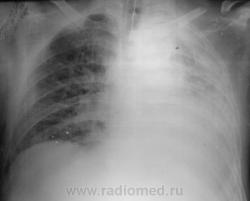

Мужчина средних лет находится в реанимации с черепно-мозговой травмой уже неделю. Сегодня при прослушивании грудной клетки дежурный врач услышал практически отсутствие дыхания слева.

ПРотсо по данному снимку, если честно, как то на ателектаз не очень похоже. (учитывая отсутсвие смещение трахеи). Мне кажется что леввосторонний гидроторакс. Вот поэтому меня и интересовало смещение средостения на лежачих снимках (особенно если укладка атипична - как случается через одного с поворотом).

сделан лёжа и я выставил в заключении ателектаз левого лёгкого, смещение средостения влево.

здесь перелом левой ключицы.

Ну, слева внизу и ребро поломано.

Возможно, гидропневмоторакс есть, но положение лежа...

Бесспорно - гидроторакс слева имеется! И, вероятно, п/травматическая(контузионная) пневмония - не забываем про ключицу с ребром(-ами)!!